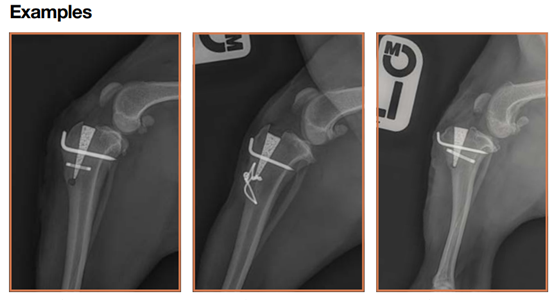

At Parkhill Vets we can treat your pet’s cranial cruciate ligament disease surgically using a geometry changing technique known as the Modified Maquet Procedure (MMP).

The Modified Maquet Procedure (MMP)

The Maquet Procedure (MP) was developed by orthopaedic surgeon, Dr P Maquet, in the 1960s to treat patellofemoral pain and knee osteoarthritis (OA) in people. The tibial tuberosity advancement (TTA) procedure is an evolution of the MP that was developed by Montavon, Tepic et al in 2002. The Modified Maquet Procedure (MMP) is an Orthomed modification of the TTA procedure used to treat cranial cruciate ligament (CrCL) deficiency-related lameness.

The MMP uses a wedge-shaped implant of OrthoFoam™ which both defines the degree of advancement of the tibial tuberosity and holds the bone in its new place while the bony ingrowth that provides permanent, biomechanically robust fixation develops. The use of a carefully engineered saw guide ensures a controlled, precisely directed and positioned osteotomy of the correct length, resulting in an appropriately “thick” tibial tuberosity while at the same time protecting adjacent structures from iatrogenic injury.

The open porous structure and sympathetic mechanical characteristics of the OrthoFoam™ wedge provides robust early and sustained bony ingrowth fixation obviating the need for bone grafting, postoperative support bandages or a lengthy period of restricted activity. The potentially disruptive forces that act to displace the distal end of the tibial tuberosity cranially following advancement are controlled using either a tension band wire or a titanium staple.